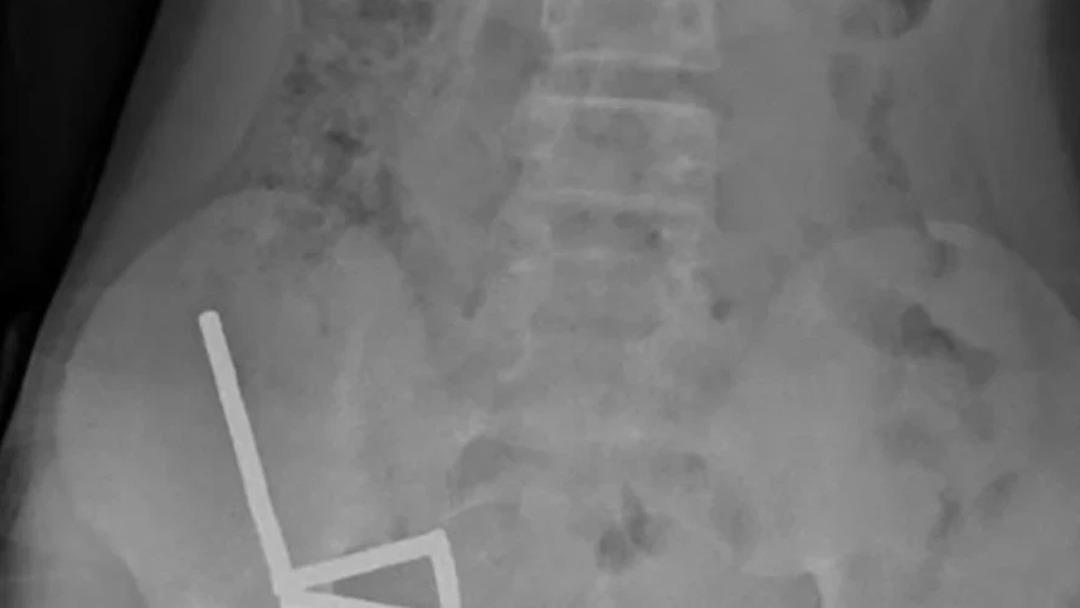

Çekilen röntgen görüntüleri, mıknatısların bağırsaklarda dört ayrı düz çizgi halinde kümelendiğini ve manyetik kuvvetler nedeniyle farklı bağırsak bölümlerinin birbirine yapıştığını ortaya koydu.

Doktorlar, mıknatısların bağırsaklarda ciddi hasara yol açtığını tespit etti. Çocuğun bağırsağının bir bölümü ve mıknatıslar cerrahi müdahaleyle çıkarıldı. Operasyon, tıp literatürüne geçti.